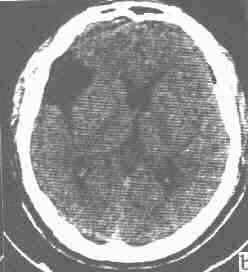

为脑外边界清楚、光滑的脑脊液密度区, CT值为 0~20 Hu,无强化表现。外侧裂池与颅穹窿附近的囊肿,内缘呈直线状为其特征,可成方形。常引起邻近颅骨的吸收和膨隆。枕大池蛛网膜囊肿可使四脑室前移位,伴病变以上脑室扩大。